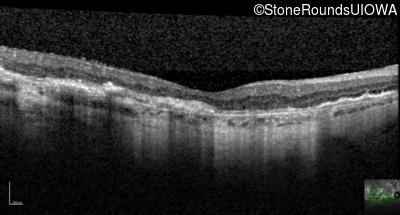

Age at visit: 64 years

This 64 year old woman first noticed some distortion in her vision at age 46 while looking at graph paper.

Age at visit: 55 years

Age at visit: 65 years

Age at visit: 66 years

Age at visit: 70 years